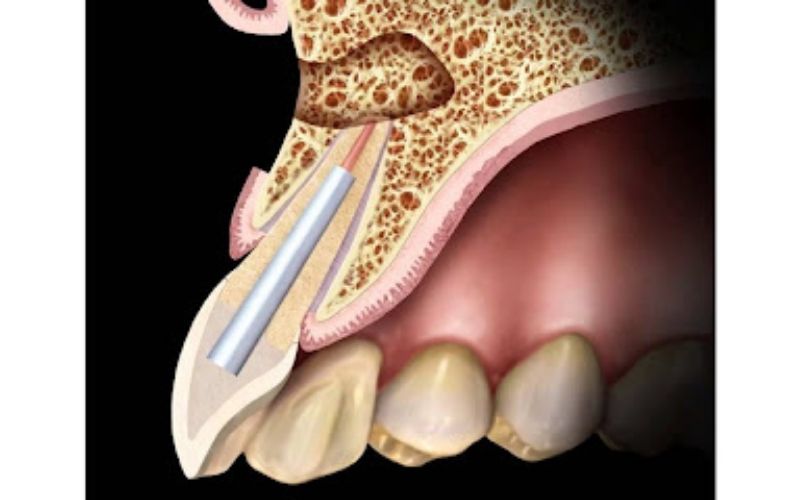

Sinüs Lift

Sinüs Lift ve Kemik Artırımı (Greftleme)

Sinüs boşluğu yükseltilip greftle kemik artırılır, implant yerleştirmek için uygun zemin hazırlanır.